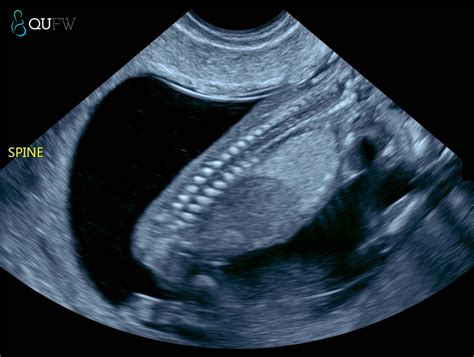

At its core, the Nuchal Translucency Screening is a specialized ultrasound scan that measures the clear space—the translucent area—at the back of your baby’s neck. During early development, all babies have some fluid in this area. However, research has shown that if this space is larger than average, it may be an early indicator of certain genetic conditions, such as Down syndrome (trisomy 21), Edwards syndrome (trisomy 18), or structural heart defects.

During the appointment, a sonographer will use an ultrasound transducer on your abdomen or, less commonly, transvaginally, to obtain a clear image of the fetus. The process is generally quick, painless, and completely safe for both the parent and the baby. The sonographer carefully measures the thickness of the fluid collection at the nape of the neck while the baby is lying in a neutral position.

💡 Note: The accuracy of the Nuchal Translucency measurement relies heavily on the baby's position; if the baby is curled up or moving too much, the technician may need a little extra time to get the perfect angle.